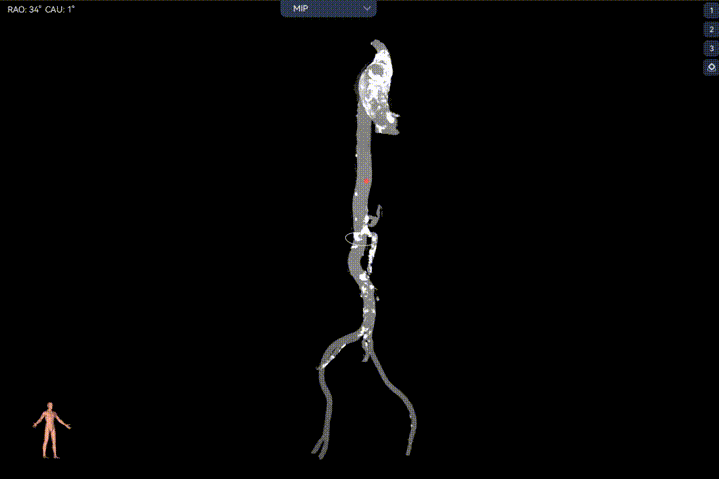

Step 2.建立大鞘通路:大鞘通过升主、边进入边加弯,避免剐蹭弓部斑块

Step 4.输送系统进入:过弓性能优异,悬空通过,整体过程未将鞘管顶起至弓顶部

过弓示意图

手术中其实有个关键点,在可调弯鞘过弓的时候,我们特意放慢了速度,一遍进一遍调弯,确保每一步都不触碰弓顶钙化。这台手术的成功,本质上是 “病变特点和器械特性” 的精准匹配。对同类型来说,碰到瓷化升主动脉合并复杂弓的病例,建议术前一定要把钙化范围、弓部角度这些解剖细节分析透,器械选择上不用局限于单一方案,多考虑协同作用,或许能找到更安全的路径。毕竟对我们来说,每台复杂手术的目标都一样:在保证安全的前提下,给患者带来最好的长期获益。